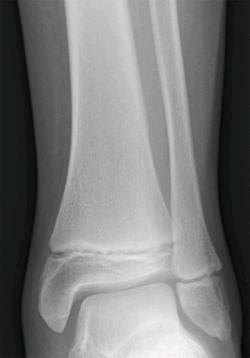

骺板:(或称为生长板)是一种位于长骨各端骨骺中的透明软骨盘。小孩与成人皆有生长板,但成人的生长板已停止生长,并被骺线取而代之。

骺软骨:为介于骨骺与骨干之间的软骨板,有生长能力 ,骨骼由此生长。

骺软骨指人类在成长时期,不规则骨和扁骨的周缘和长骨两端与骨干相接的部位,未发生骨化的板状软骨。

骺软骨不断分裂增殖并不断骨化,使骨不断的加长和扩大。全身各骨的骺软骨到16-20岁左右全部停止增殖并骨化,骺软骨随之消失,从此长骨不再增长,不规则骨和扁骨不再扩大,当骨骺与骨干融合成一整块骨后,两者连接处的表面留有一条线叫骺线,骺线形成后,骨的长度就不再增长。

骺软骨能不断增生,又不断骨化,使骨的长度增加。成年后骺软骨骨化,原骺软骨处形成一线状痕迹,称为骺线。

儿童时期骺软骨损伤可发生不同程度的骨发育畸形。